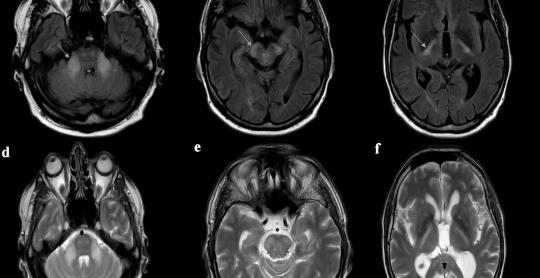

Journal of Neurology Research

Vol. 15, No. 3, Aug 2025, pages 130-134

By Slaven Pikija et al.